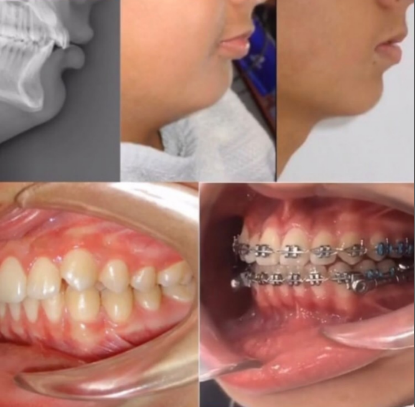

НАШИ РАБОТЫ УСТАНОВКИ СИСТЕМЫ БРЕКЕТОВ